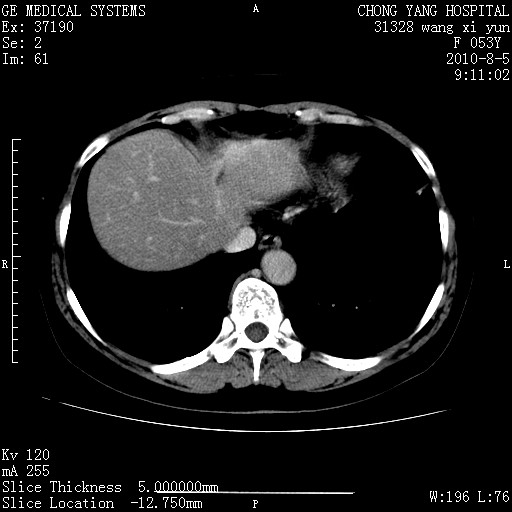

标题: CT28214:F41Y 血尿二十天,建议盆腔平扫加增强。

1)考虑肝左叶胆管细胞癌。2)脂肪肝。